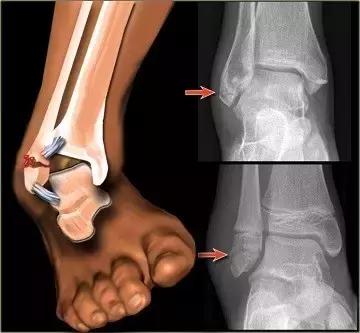

此时可前后轻轻活动踝关节,感觉是否有明显的活动障碍;轻轻的按压局部皮肤,感觉是否有明显的压痛点、条索状物、碎片状物等。

如果有,则存在骨折、骨裂、韧带附着端撕裂的可能性很大。当然,仅凭主观感觉难以100%确认,待伤情平稳后可到外科门诊行X光检查,以明确诊断。